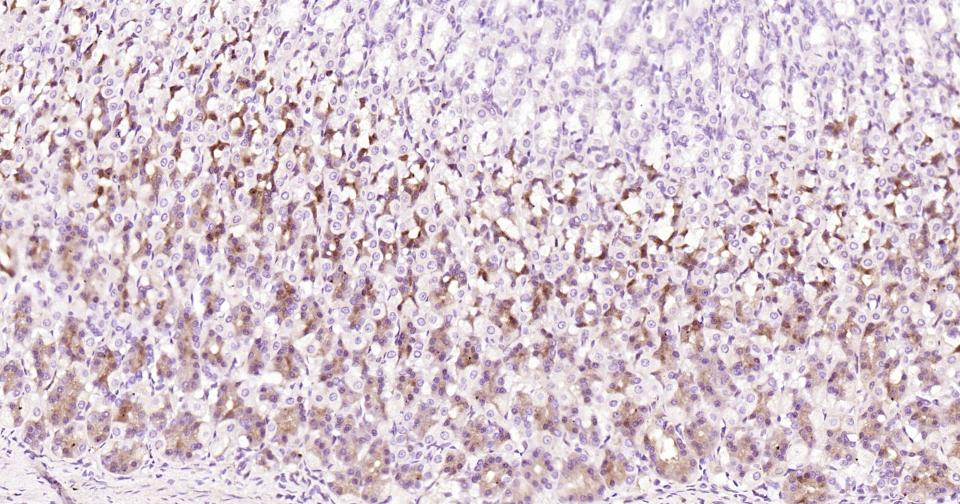

Paraformaldehyde-fixed, paraffin embedded Mouse Stomach; Antigen retrieval by boiling in sodium citrate buffer (pH6.0) for 15 min; Antibody incubation with Notch1 Monoclonal Antibody, Unconjugated(bsm-60871R) at 1:200 overnight at 4°C, followed by conjugation to the bs-0295G-HRP and DAB (C-0010) staining.